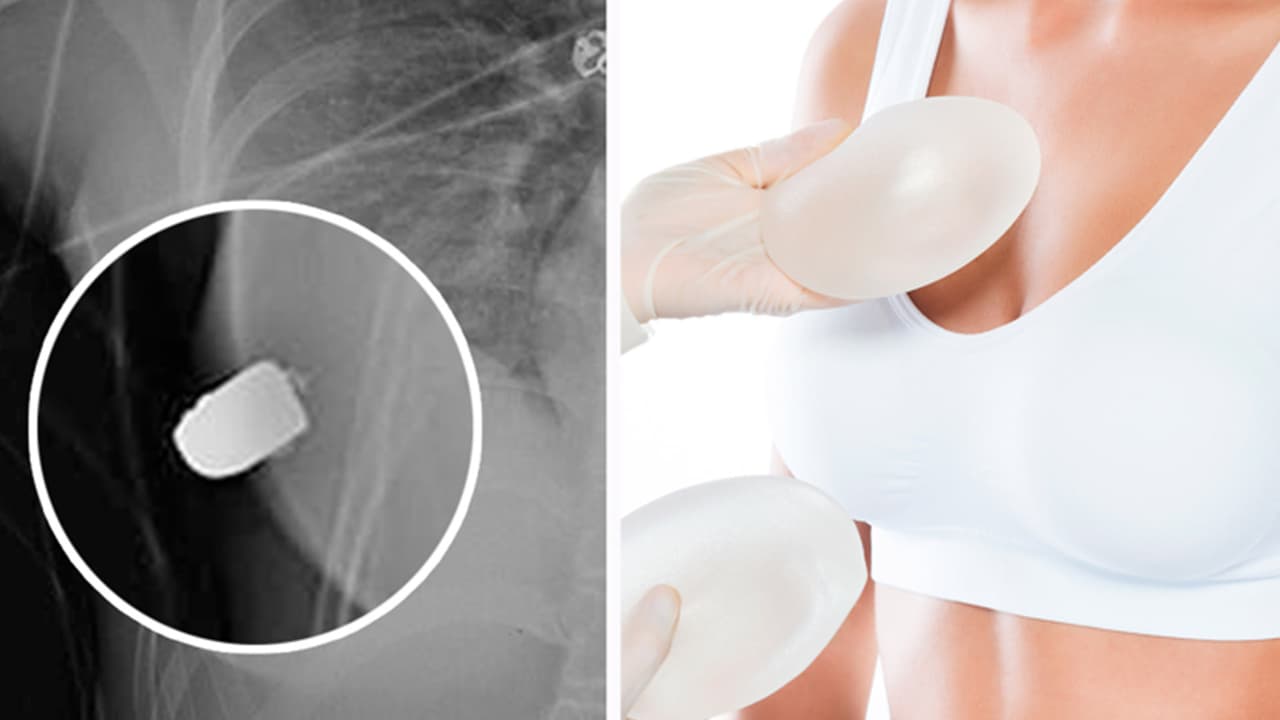

Implante de seno salva a mujer de un balazo en el corazón

Mientras la víctima caminaba por las calles de Toronto, de repente sintió calor y ardor en su pecho, por lo que solicitó apoyo médico de urgencia y al revisarla, los doctores se sorprendieron con lo que encontraron.